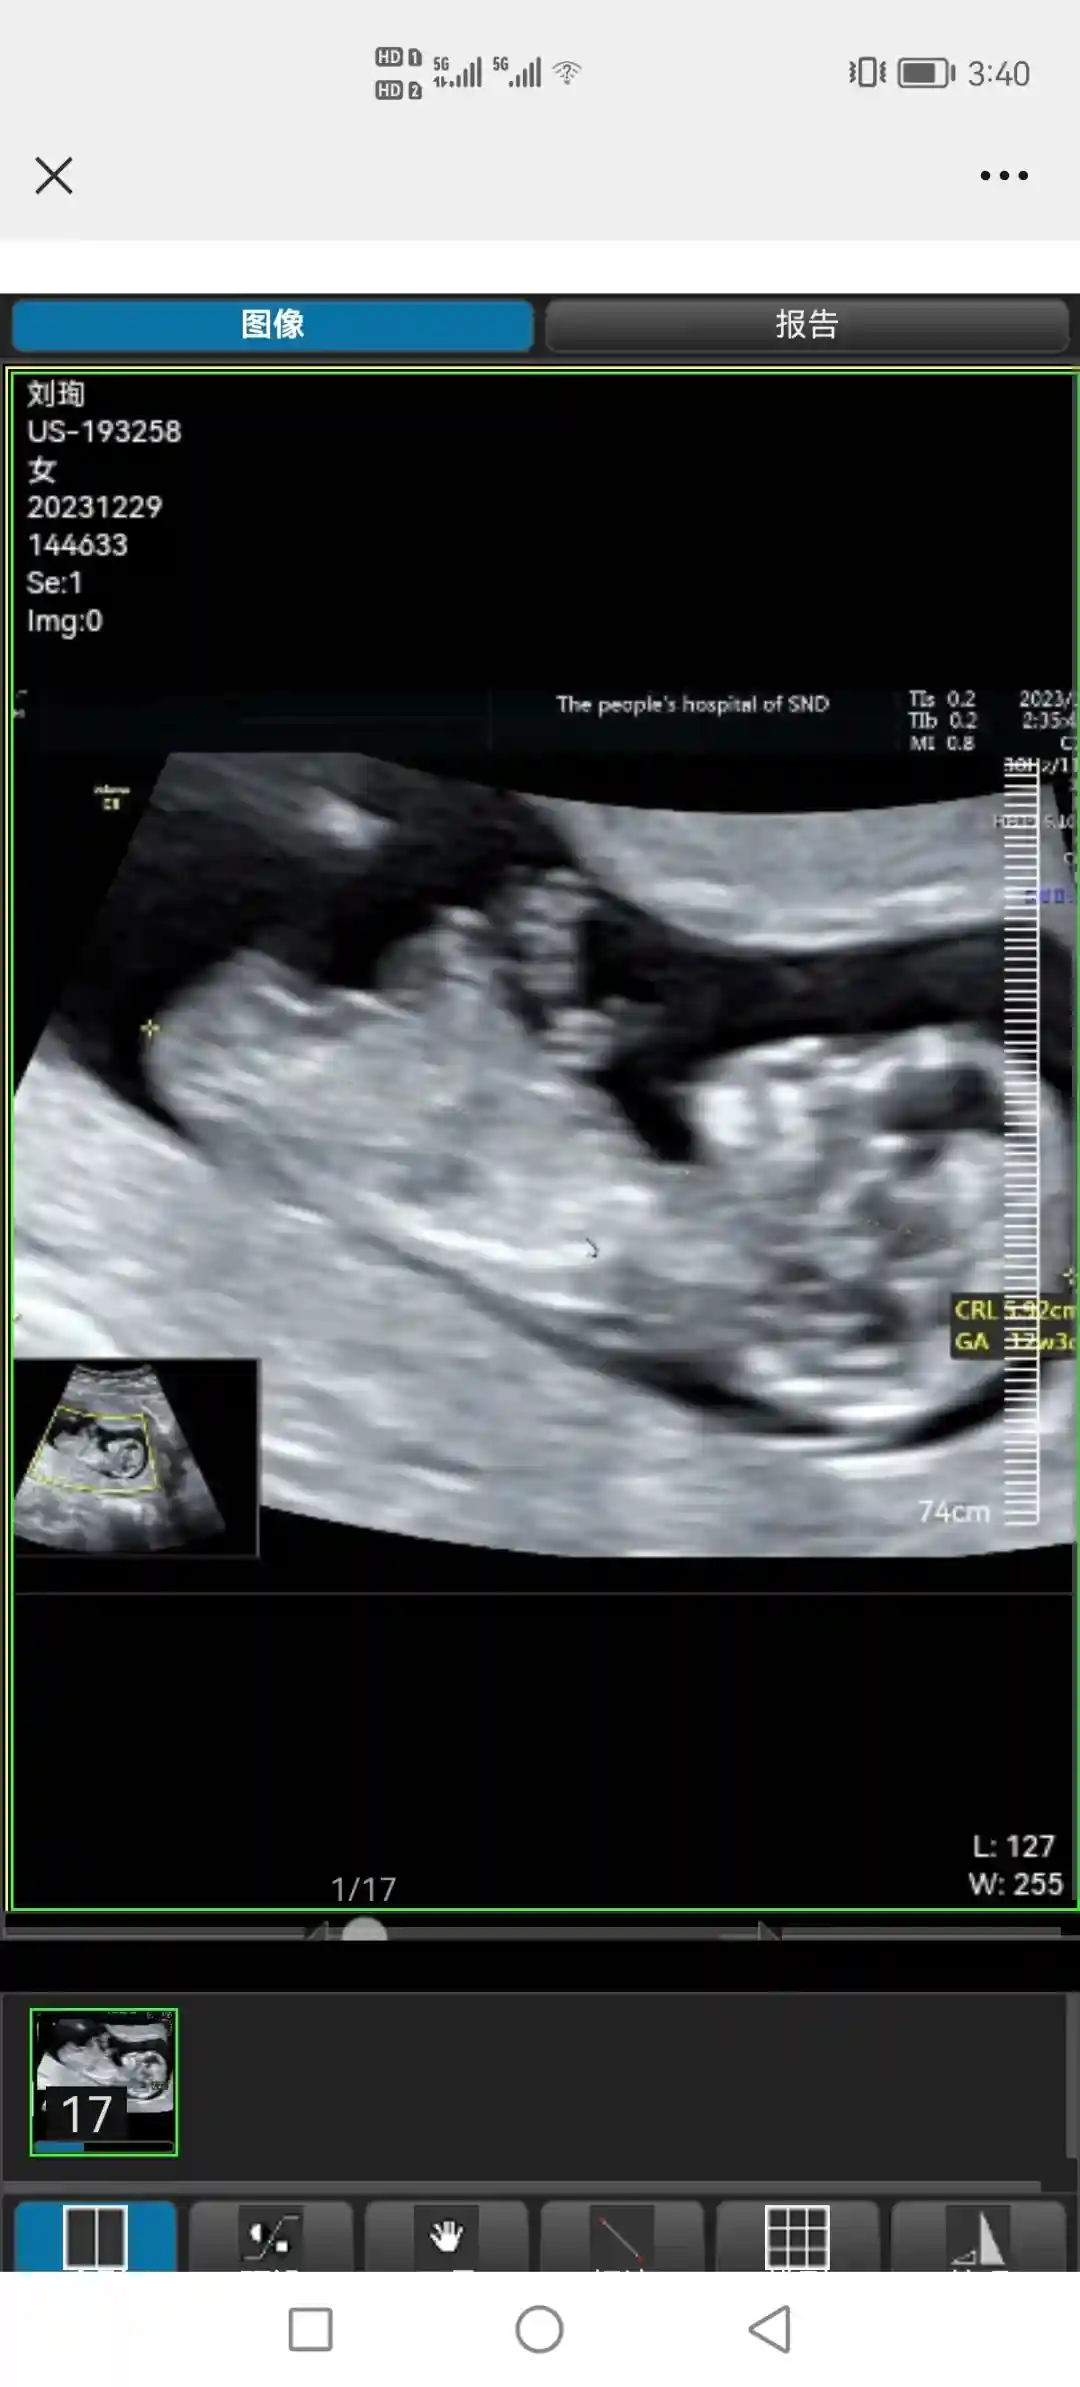

-2023年4月份,医生说可以怀孕了。我算好排卵期,一次就中了。但这次着床不好,指标不好出血、流产了。流产后,医生说如果时间允许的话,休养1个月最好。然后我真的在家休养了一个月,不碰冷水、不干活,以至于身体恢复得很好。(感恩公司给我这么久的休假,还有我给力的队友和公婆)。我去复查的时候,医生说,你这养得白白胖胖气色很好啊哈哈!保守起见,医生让我过半年再准备怀,于是半年后算好时间,又是一次就中了。(图2是12周左右)